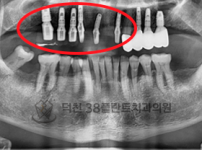

치료전후